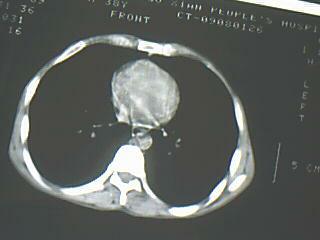

以下是引用随光逐影在2009-8-7 15:40:00的发言:[br]考虑右肺继发性肺结核并右肺上叶空洞形成,两肺支气管播散;不排除右肺上叶空洞内霉菌感染可能。

以下是引用jiangjing在2009-8-7 14:38:00的发言:[br]右上肺张力空洞,酐珞坏死灶,支气管扩张,多发播散灶,纵膈淋巴结显示,胸膜增厚---结核